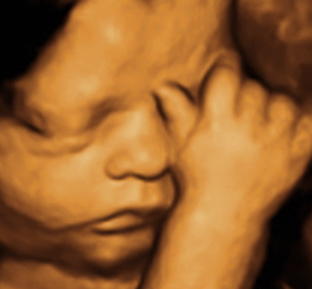

Baby scan image 1